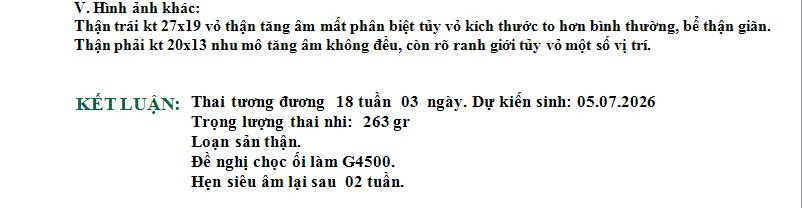

Chị H. đến phòng khám Dr Tú y học bào thai vào một buổi chiều muộn khi thai được 21 tuần. Trên tay chị là tờ kết quả siêu âm vừa làm buổi sáng. Dòng mô tả ghi thận phải tăng âm, cấu trúc không đồng nhất, cấu trúc không đồng nhất,nghi loạn sản thận.

Bác sĩ bắt đầu bằng việc xem lại toàn bộ hình ảnh siêu âm mà chị mang theo. Sau đó siêu âm lại một cách cẩn thận, dựng các mặt cắt chuẩn của hai thận, đo kích thước từng thận, quan sát bàng quang và đánh giá lượng nước ối.

Giai đoạn 20–24 tuần là thời điểm thận đủ lớn để quan sát rõ trên siêu âm. Bác sĩ có thể nhận diện:

- Thận tăng âm thai nhi

- Thận có nang

- Cấu trúc không đồng nhất

- Ranh giới vỏ tủy mờ

- Kích thước bất thường

Siêu âm giúp đánh giá hình thái nhưng không đo trực tiếp chức năng thận của thai nhi. Vì vậy nhiều trường hợp chỉ được ghi nghi Loạn sản thận và cần theo dõi thêm.